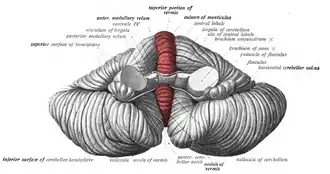

Vermis (highlighted in red) on the cerebellum. | |

The cerebellar vermis (from Latin vermis, "worm") is located in the medial, cortico-nuclear zone of the cerebellum, which is in the posterior fossa of the cranium. The primary fissure in the vermis curves ventrolaterally to the superior surface of the cerebellum, dividing it into anterior and posterior lobes. Functionally, the vermis is associated with bodily posture and locomotion. The vermis is included within the spinocerebellum and receives somatic sensory input from the head and proximal body parts via ascending spinal pathways.[1]

Structure

The vermis is the unpaired, median portion of the cerebellum that connects the two hemispheres.[9] Both the vermis and the hemispheres are composed of lobules formed by groups of folia. There are nine lobules of the vermis: lingula, central lobule, culmen, clivus, folium of the vermis, tuber, pyramid, uvula and nodule.[9] These lobules are often difficult to observe during human anatomy classes and may vary in size, shape and number of folia. It has been shown that folia of the cerebellum exhibit frequent variations in form, number and arrangement between individuals.[9]

Lobe anatomy

The lingula is the first lobule of the upper portion of the vermis on the superoinferior axis and pertains to the paleocerebellum together with the central lobule, culmen, pyramid and uvula. It is separated from the central lobule by the pre-central fissure. The central lobule is the second lobule of the upper portion of the vermis on the superoinferior axis. The culmen is the third and largest lobule of the upper portion of the vermis on the superoinferior axis. It is separated from the declive by the primary fissure and is related with the anterior quadrangular lobule of the hemisphere. The pyramid is the seventh lobule of the vermis on the superoinferior axis. It is separated from the tuber and uvula by the pre-pyramidal and secondary fissures, respectively.[9] This lobule is related with the biventral lobule of the hemisphere. The uvula is the second largest lobule, following the culmen. It pertains to the paleocerebellum and is separated from the nodule by the posterolateral fissure.[9]